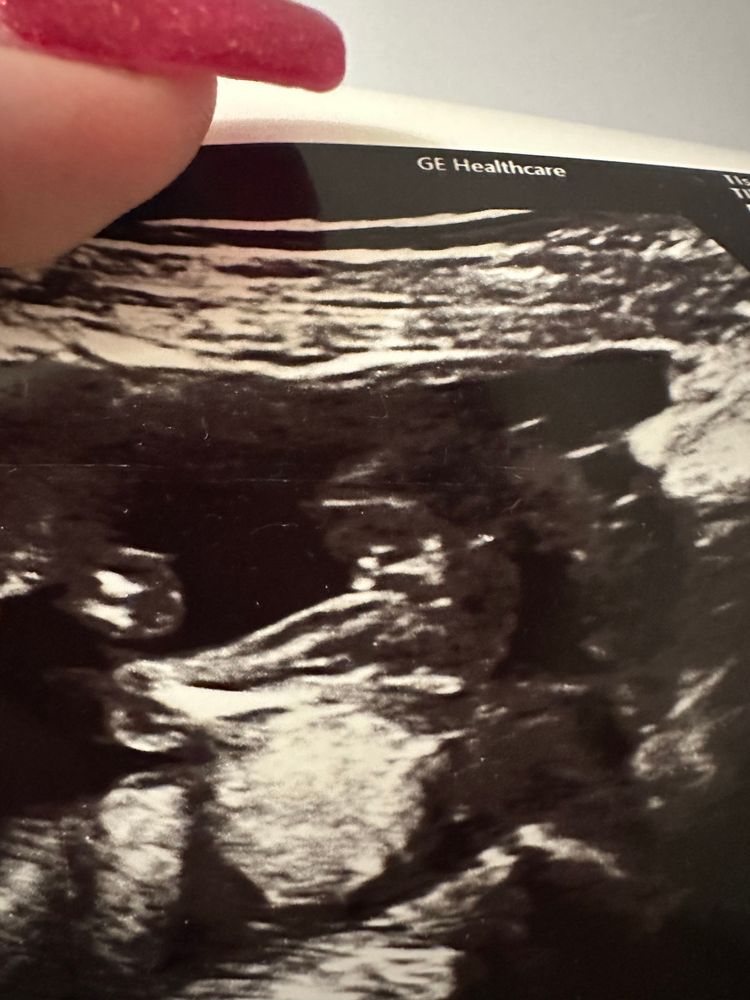

Мальчик или девочка ? Узи снимок 11 недели мальчик или девочка врач не сказала,. А я так хочу узнать. Кто то понимаеть

УЗИ мальчик или девочка

Ещё бы понимать, где тут что